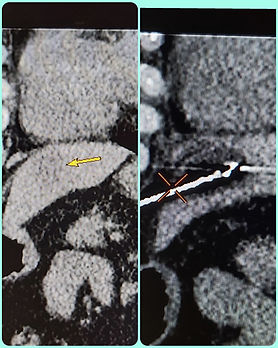

Kalbe yakın komşulukta olan bir karaciğer metastazına kriyoablasyon tedavisi

Kriyoablasyon uygulanan bir hastamızın işlem sırasına alınan görüntüsü

Kriyoablasyon uyguladığımız bir hastada karaciğeğrdeki lezyonun işlem öncesi ve sonrası görüntüsü